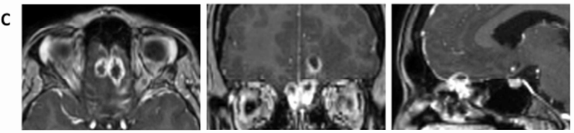

然而,5个月后再次复查MRI,发现肿瘤体积再次显著增大,病变已累及筛窦及额叶实质(图1D)。

图1D:第二次活检后5个月,病灶再次增大

手术不能再等,2014年10月我接受手术治疗。手术台上,医生们发现这个病灶硬得像石头,但好在医生帮我把脑子里的病变全部切除。

术中行双侧额部冠状切口,采用额下入路。病灶质地极硬,与周围炎性纤维化组织分界清晰,可完整分离,外观酷似曲霉性肉芽肿;遂行病灶全切除。受累硬膜附着区予电凝并彻底清理。因术中冰冻切片未见恶性证据,且无需肿瘤学意义上的扩大切除,筛窦结构予以保留完整。术后MRI(图2A)示颅内病灶已全切,但嗅球周围仍有持续强化灶。

图2A:术后MRI示额部肉芽肿已完整切除